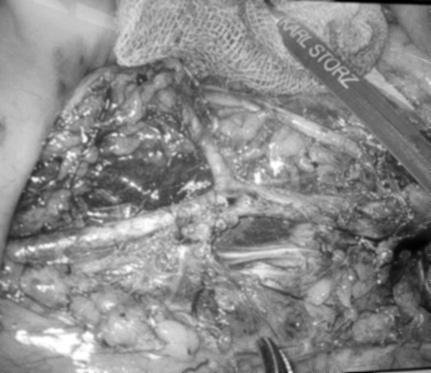

完成肠系膜下动、静脉及左结肠动脉游离裸化

红圈处为肿块